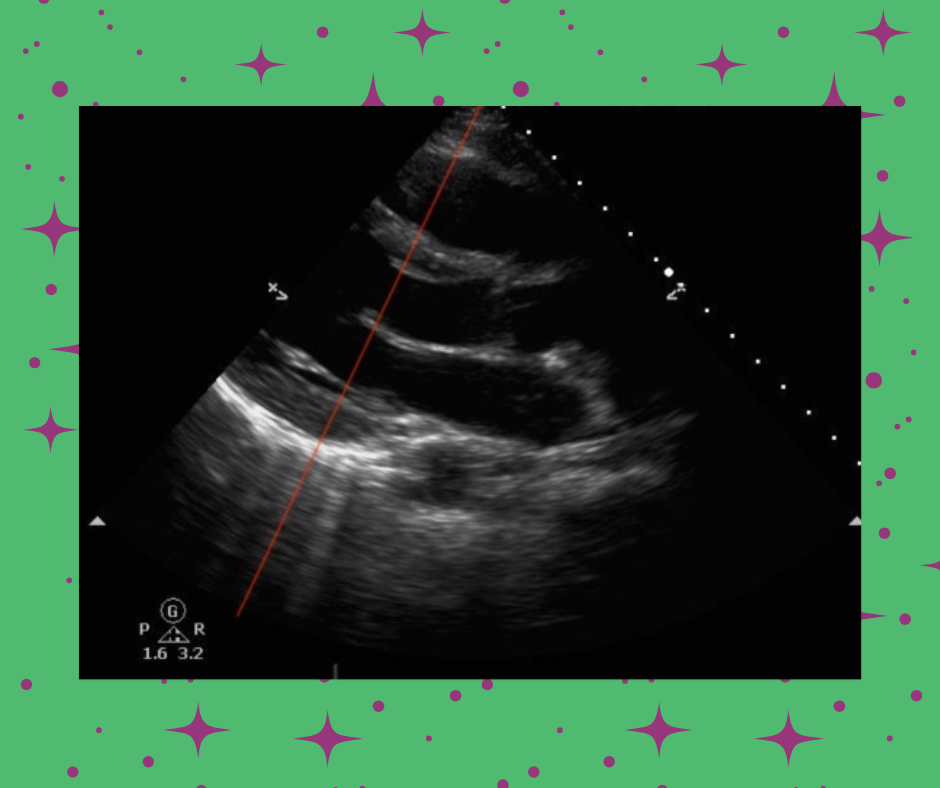

Advanced Critical Care Ultrasound: E-Point Septal Separation to Estimate Left Ventricular Ejection Fraction

Emergency physicians have been shown to be accurate at visual estimation of the left ventricular ejection fraction without quantitative measurements. However, there is still value in a quick and easy quantitative measurement of the LVEF.